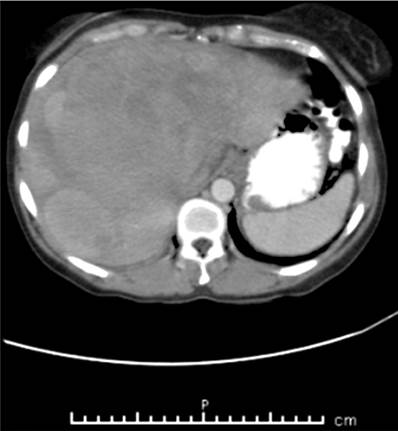

Se tomó TAC de abdomen contrastado y se encontró hígado de tamaño normal con contorno lobulado y ecogenicidad heterogénea. Se observaron 3 lesiones de predominio isodenso con el parénquima, con algunas áreas de menor densidad al interior, localizada de mayor tamaño en los segmentos 5, 7 y 8, que medían 149 x 128 mm; y otras 2 lesiones hacia los segmentos 2 y 7, con diámetros de 51 y 57 mm; hallazgos que sugieren cambios por proceso neoplásico. El resto de los órganos abdominales se encontraban sin alteraciones (Figura 2).

Es muy difícil diagnosticar melanoma primario del tracto digestivo. Los criterios diagnósticos sugeridos son ausencia de otra ubicación de melanoma y de nevos cutáneos atípicos, lesión localizada solo en el intestino delgado, sin metástasis a distancia y la presencia de un foco primario en la mucosa. Las metástasis en el hígado y el duodeno fueron identificadas en la paciente (Figura 2 y 3) después de un análisis detallado de todos los demás lugares posibles del foco primario. Este no se pudo identificar, por tanto, se hizo diagnóstico de melanoma de origen primario desconocido.

Cuando se sospecha metástasis de melanoma en el tracto digestivo se debe llevar a cabo el diagnóstico por imágenes apropiadas. La primera etapa básica de diagnóstico es la ecografía abdominal, este es un examen no invasivo y de bajo costo. Otro examen es la tomografía computarizada, cuya sensibilidad de identificación de metástasis de melanoma en el tracto digestivo es solo de 60%-70%. En cada caso, cuando las metástasis en el tracto digestivo se sospechan clínicamente, es necesario llevar a cabo otros exámenes a pesar de TAC negativo. El examen PET/TC garantiza mayor sensibilidad que la TAC en la identificación de metástasis de melanoma y debe llevarse a cabo si está disponible 4. En el reporte de caso, la ecografía y la TAC revelaron metástasis en el tracto digestivo (Figura 1 y 2).